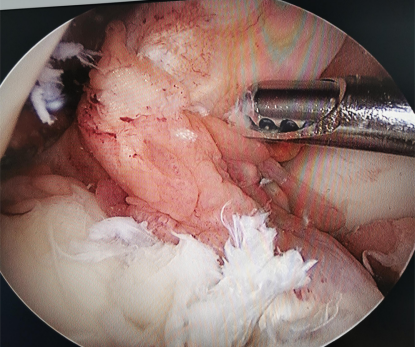

半月板损伤修补术